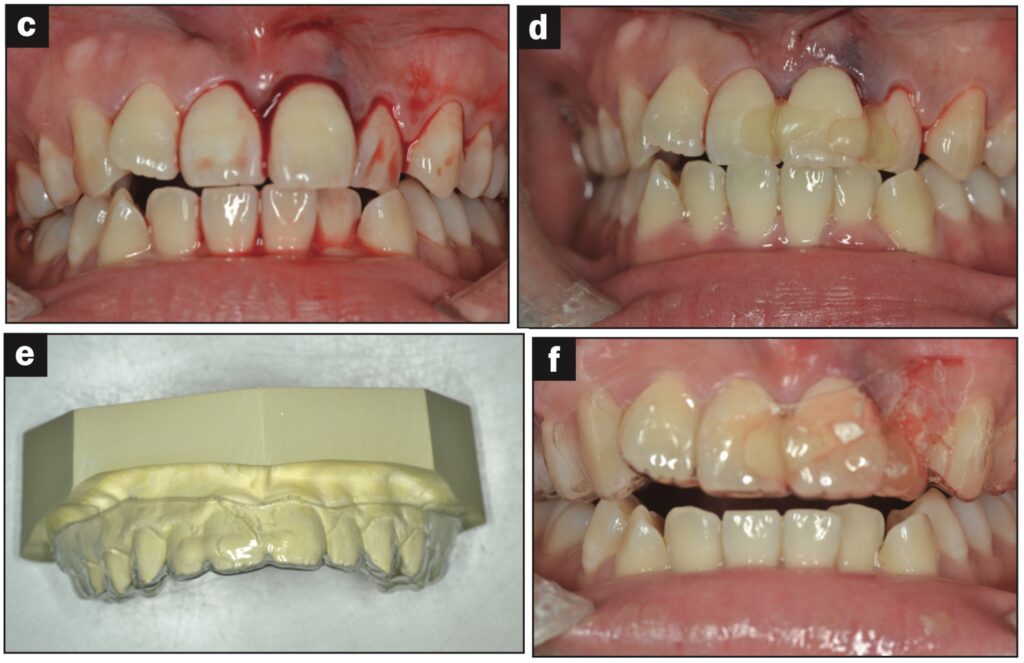

Bệnh nhân nữ 24 tuổi bị ngã khiến răng cửa giữa hàm trên bên trái bị lệch sang một bên. Sáng hôm sau, bệnh nhân đến phòng khám, được cố định bằng composite quang trùng hợp và lấy dấu.

Sáu tiếng sau, bệnh nhân quay lại và nhận hàm duy trì.

Bệnh nhân được hướng dẫn đeo hàm duy trì cả ngày trừ khi đánh răng. Các thử nghiệm độ sống tủy được thực hiện sau 1, 7, 14 và 21 ngày. Kiểm tra độ lung lay răng, gõ, sờ, thử tủy EPT và chụp X quang sau 28 ngày. Răng có độ lung lay +1 theo chiều ngoài trong và không có đáp ứng với thử nghiệm tủy EPT.

Ba tháng sau, răng đã được trám phục hồi và đáp ứng EPT (8/10). Tại thời điểm tái khám sau 4 tháng, răng đáp ứng với EPT (4/10). Sau 5 tháng, ghi nhận có lỗ dò. Răng không đáp ứng với EPT. Tổn thương quanh chóp được nhìn thấy trên X quang.

Răng được chẩn đoán là hoại tử tủy và điều trị tủy được thực hiện trong 2 lần hẹn. Một tháng sau (6 tháng sau khi chấn thương xảy ra), lỗ dò biến mất và chụp X quang cho thấy quá trình lành thương (hình 2).